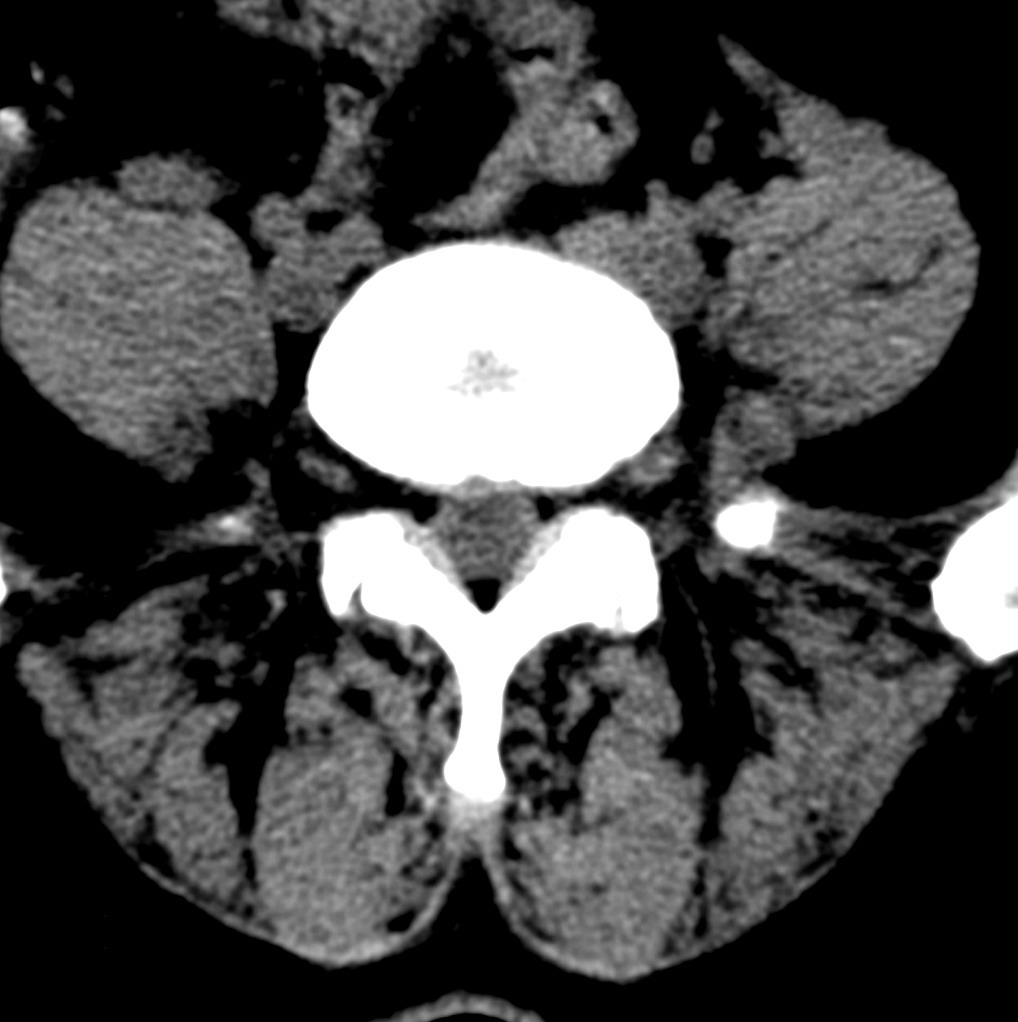

标题: CT19570:是否为腰脱? [打印本页]

标题: CT19570:是否为腰脱?

可以定腰脱否?

大于椎体的环状软组织影,椎间盘膨出

椎间盘膨出伴突出

支持间盘膨出伴突出。

双边征,考虑滑脱。

椎间盘突出

腰脱证据不足。

椎间盘膨出伴突出!

椎间盘突出,

椎间盘改变并不是很明显,黄韧带似乎有肥厚,